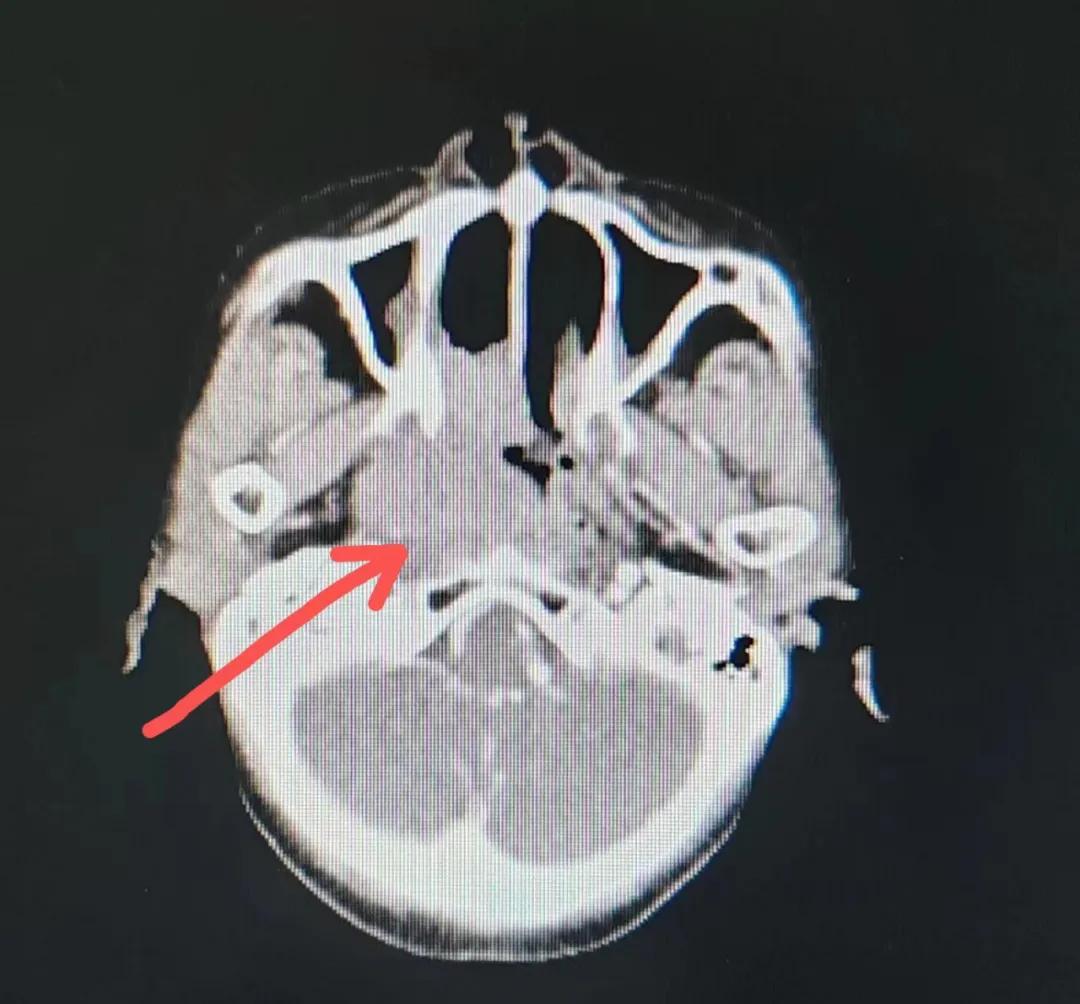

70歲的彭阿姨,5個月前因鼻部瘙癢伴流血不止在當地診所治療,瘙癢和出血癥狀不但沒有得到有效控制,反而進行性加重,并出現鼻腔堵塞、進食困難,經外院病理活檢確診為“鼻腔惡性淋巴瘤”。不斷加重的病痛已嚴重影響了老人的生活質量,為求診治,患者及家屬于今年2月份慕名來到了市二院放療科。

治療前

老人因鼻部腫物堵塞鼻腔并且侵犯鼻咽導致鼻塞、疼痛、吞咽困難,身心都備受煎熬,趙亮主任在詢問其病史期間幾度落淚。趙亮主任向患者及家屬解釋說:“現代放療比過去的傳統(tǒng)放療設備先進,技術不斷提升,能對腫瘤區(qū)域的照射劑量進行優(yōu)化,做到準確定位、精準照射,同時,最大限度地降低正常組織的受量,對全身情況影響很小。”

考慮到患者年齡較大、體質差,手術難度大,且常規(guī)的放射治療難以保護患者晶體造成患者雙眼視力損傷,放療團隊以最快的速度制定了精準放射治療方案并開始為其實施治療。僅僅數日后,老人腫塊出血即得到控制,腫塊明顯縮小,放療20次后腫塊迅速縮??!